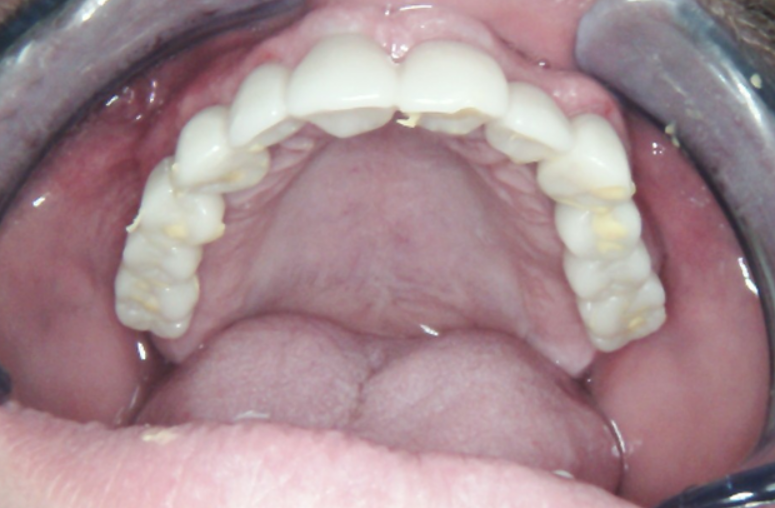

Two weeks after implant placement, a temporary removable prosthesis was delivered. During this phase, the implants remained non-loaded to allow for undisturbed osseointegration. The prosthesis was carefully designed to support the gingival contours and preserve the interdental papillae, a key factor for achieving optimal esthetics in the final restoration.

The planned final maxillary restoration will consist of several independent zirconia bridges. Separating the posterior and anterior segments in this way creates shorter lever arms, which reduces torque and stress on the implants, preventing loosening and overload.

Currently, the patient is wearing the provisional PMMA prosthesis. He is attending regular professional hygiene appointments and adhering to a strict home care regimen. This transitional period allows for the evaluation of the function and esthetics of the PMMA prosthesis, so that any necessary adjustments can be made before fabricating the final restoration, ensuring an optimal outcome.